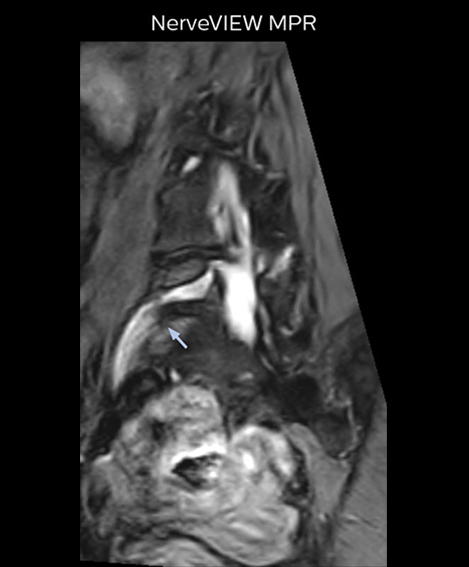

“For example, in sagittal images, when the presence of fat is observed in the intervertebral foramen, it suggests that there is a margin around the nerve. Similarly, the absence of fat indicates that the nerve is being compressed. So, we used to deduce nerve compression indirectly. With NerveVIEW, however, we can observe the condition of the nerves directly, regardless of the presence or absence of fat. We always prefer such direct observation of anatomy over having to make an inference about it.”

“Although symptoms of typical disc herniation and atypical hernia are very similar, the actual site of herniation is different. It is therefore important to characterize the nerve’s condition both inside and outside of the intervertebral foramina. “Conversely, if we see no abnormality in NerveVIEW, we can assume at least that there is no severe condition that requires surgery. Like this, it can help us avoid unnecessary surgery. NerveVIEW can have a tremendous impact in this way.”

“The intra-luminal signal of veins, especially around the intervertebral space, can be suppressed well with NerveVIEW. As a result, we can easily observe the detailed nerve structure around the posterior ganglion,” he says. “This is why we use 3D NerveVIEW for intraforaminal stenosis and extraforaminal stenosis/herniation (lateral disc herniation). On the other hand, if herniation is suspected to exist inside the dorsal root ganglion (DRG), balanced TFE or ProSet-FFE is applied. NerveVIEW is not suitable for evaluating the median type of herniation.” The SE-EPI DWI-based method for MR neurography works well for large FOV exams like whole-body MRI, but focal examination of nerves is often limited by the attainable spatial resolution (both inplane and slice direction) and geometric distortion. “3D NerveVIEW achieves higher in-plane resolution – close to our other routine spine sequences – and the source images can be used instead of adding a fat-suppressed T2-weighted sequence,” Tanji says.

“Recently, the two surgical methods extreme and oblique lateral interbody fusion (XLIF and OLIF) have become mainstream for minimally invasive treatment of lumbar spinal canal stenosis and intervertebral foramen stenosis. With these surgical techniques, the spine is approached from the flank, and prior knowledge of the exact anatomy of the lumbosacral plexus would be extremely helpful. To that end, high slice resolution (less than 1 mm acquisition) that enables sharper sagittal MPR images will be needed.”

“For both brachial and lumbar plexus, we are currently using a 230 mm FOV and voxels of about 1 x 1 x 2 mm acquired (1 x 1 x 1 mm reconstructed). This provides us a good representation of the nerves, even though this FOV is relatively small. Regarding the inplane resolution, we hope to be able to bring that down to 0.7 mm, similar to our typical 2D multislice T2W images,” says Tanji.